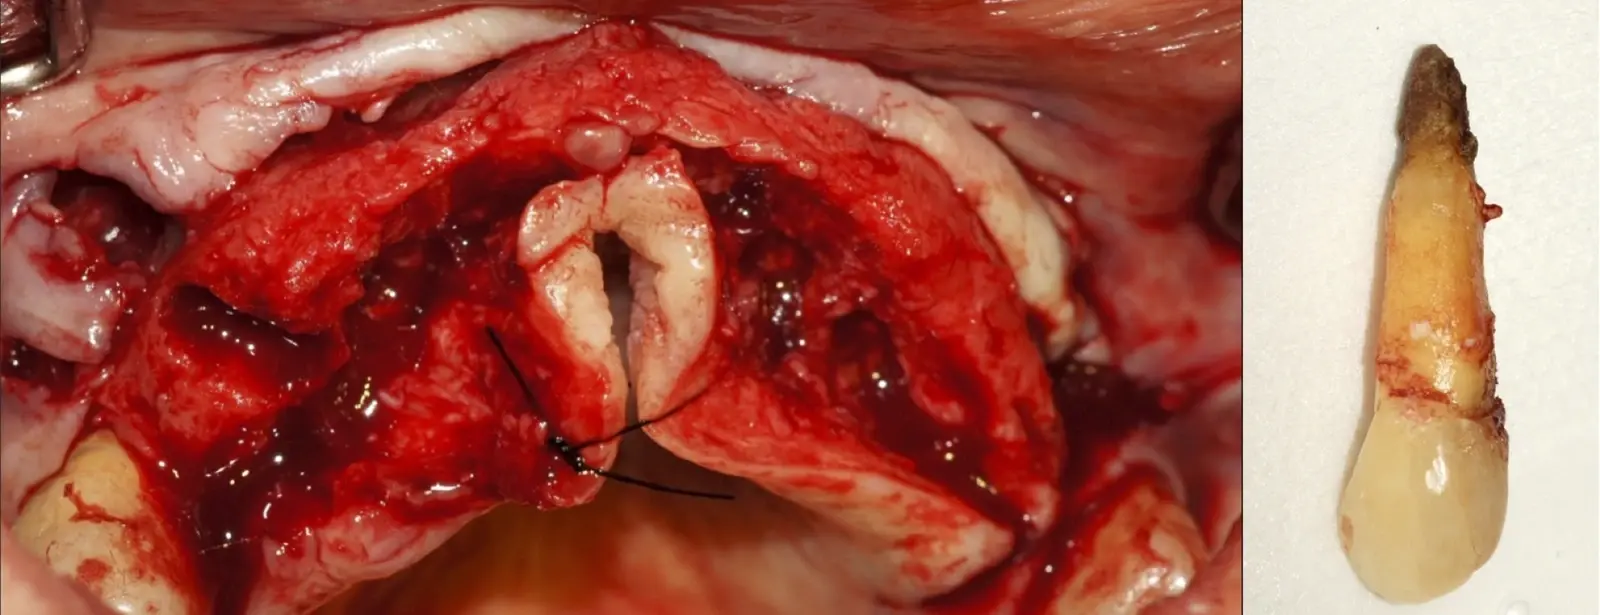

El procedimiento se inicia colocando anestesia y elevando un colgajo mucoperióstico a espesor completo3 (incisión semilunar o intrasurcular con/sin protección papilar) y exponiendo la zona. En seguida se realiza la enucleación de la lesión, eliminando16 o creando una ventana17 en la lámina cortical que contiene el área del ápice; este retiro óseo se realiza con los insertos de forma aplanada dentada o inserto con cobertura diamantada plano o redondo, recordando ser lo más conservador posible (Figura 5).

Después de realizado el acceso e identificado el ápice, se procede a la limpieza de la zona con instrumentos manuales y/o con insertos diamantados de parte activa angulada para poder eliminar todo el tejido patológico del perímetro radicular apical y del tejido óseo circundante (Figura 6).